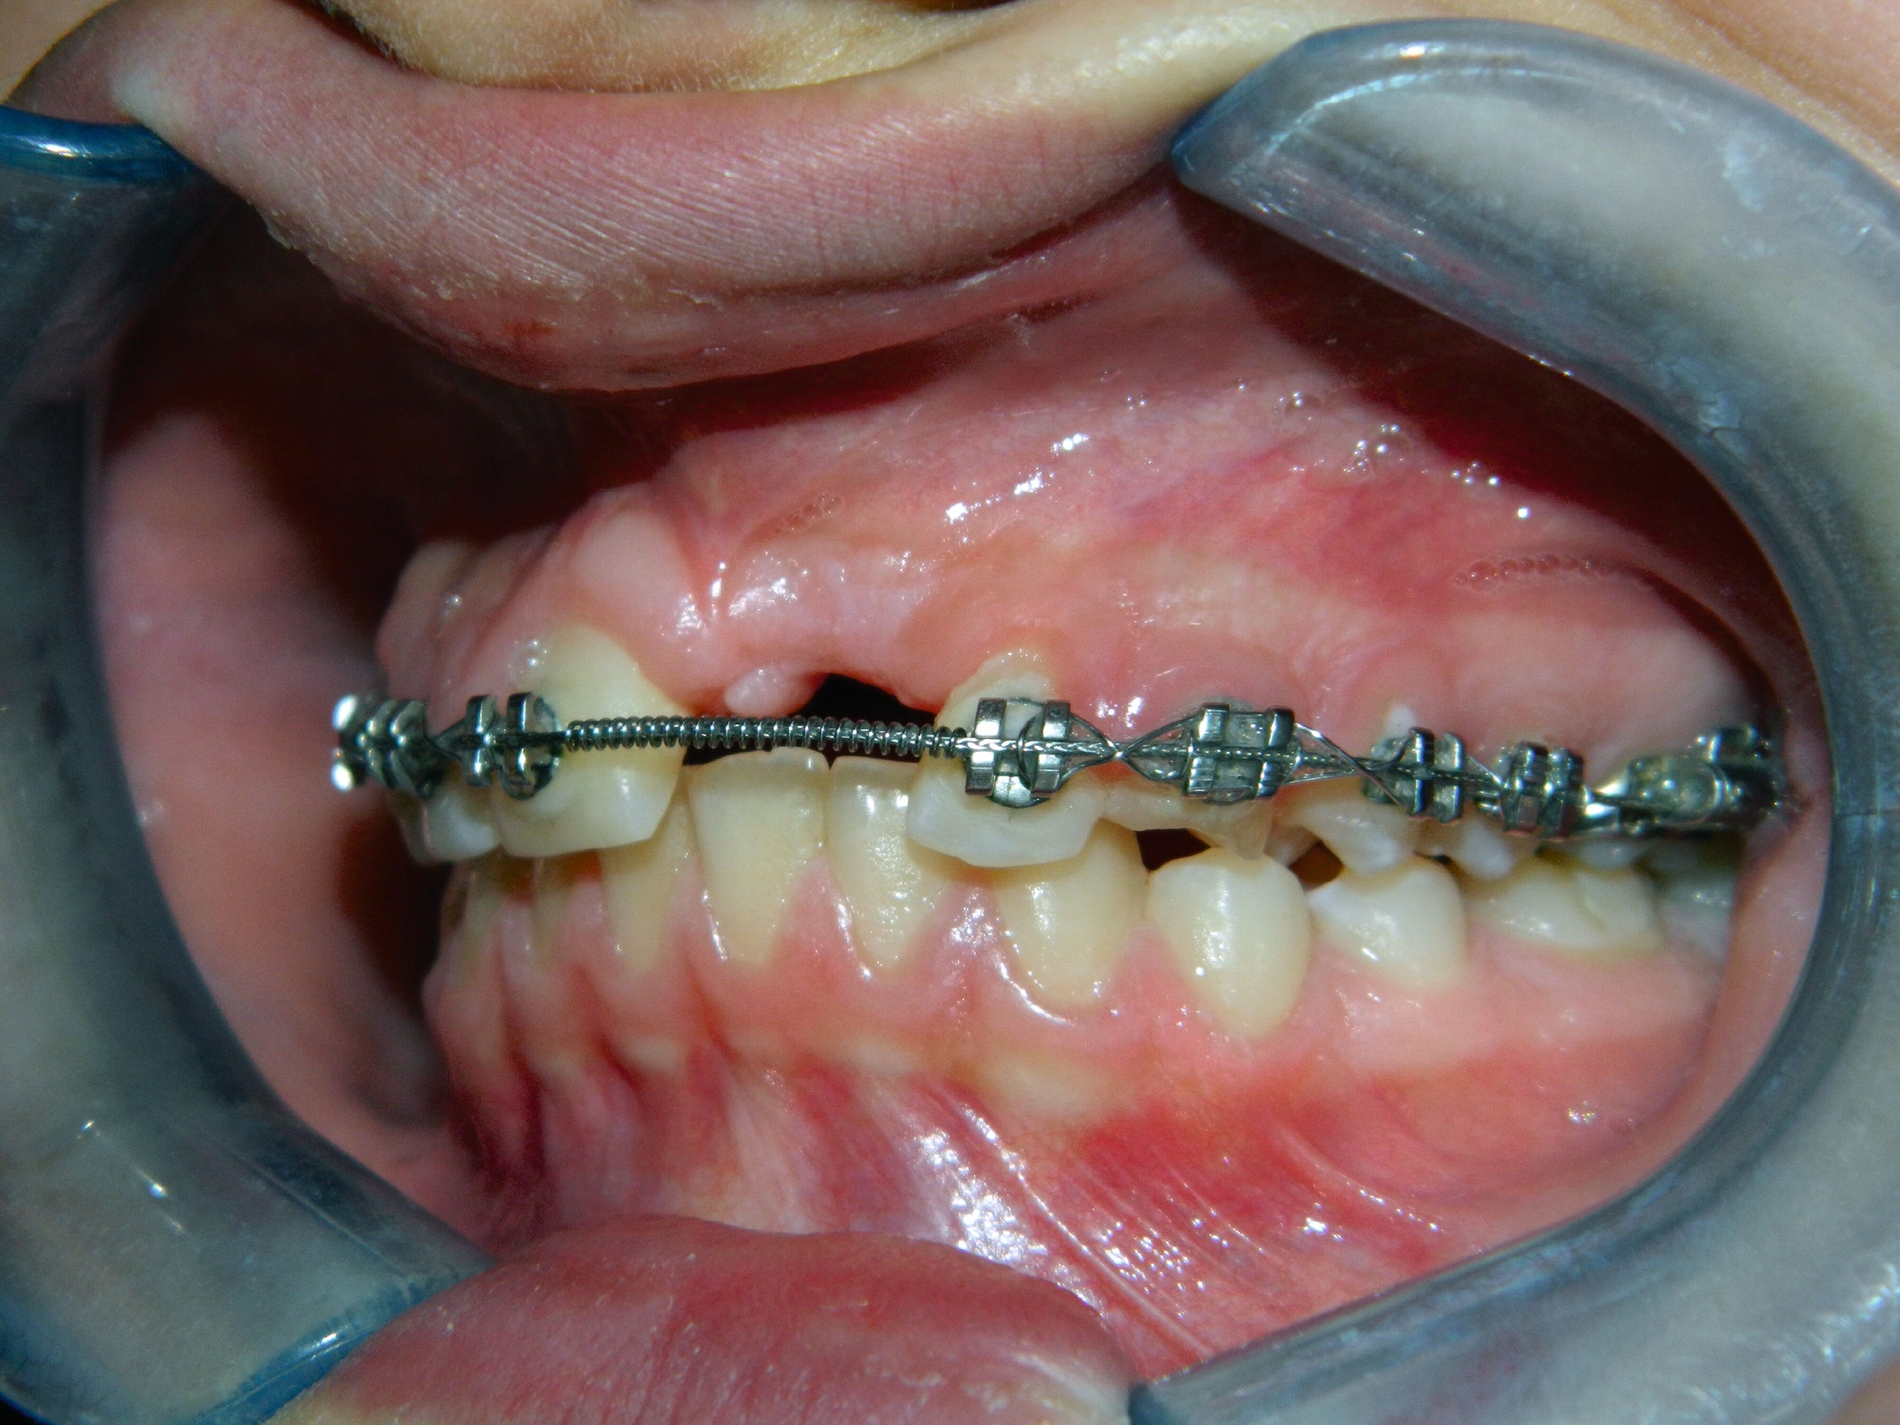

Um die Position des impaktierten Eckzahns zu beurteilen, wurde zehn Monate nach der Extraktion des Schneidezahns eine weitere Panoramaröntgenaufnahme angefertigt, Die Position des Eckzahns war unverändert, jedoch hatte die Extraktion des impaktierten oberen Schneidezahns zu einer signifikanten Knochenresorption und Atrophie des Alveolarkamms (Abbildung 3) geführt.

Nach einer detaillierten Analyse des Falles wurde als Ziel der Behandlung die chirurgische Freilegung und Aufrichtung des impaktierten Eckzahns im Bereich des extrahierten linken mittleren Oberkieferschneidezahns festgelegt. Um die Höhe und die Breite des Alveolarkamms wiederherzustellen und eine adäquate Unterstützung der Gingiva zu gewährleisten, war die Augmentation des Alveolarkamms notwendig. Die Patientin wurde dafür an die Klinik für Mund-, Kiefer- und Gesichtschirurgie des Universitätsklinikums des Saarlandes überwiesen.

Drei Wochen nach der Operation wurde mithilfe eines modifizierten Palatinalbogens mit einem verlängerten Palatinalarm mit der Traktion des Eckzahns begonnen (Abbildung 4).